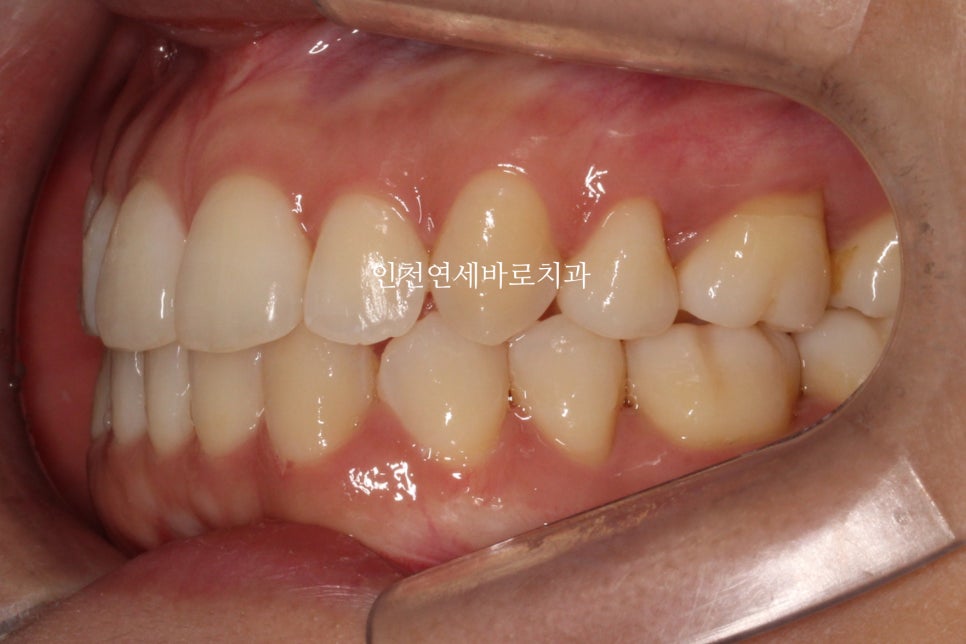

선천적결손치아가 있던 환자분이며, 웃을때 사진을 보면 약간의 비대칭도 관찰됩니다.

아래 앞니가 없다보니 중심선도 안맞고, 아래 치아의 사이즈도 양쪽이 다름을 알 수 있습니다.

비대칭이 있다보니 위쪽 치아가 전체적으로 기울어져 있는것도 확인됩니다.